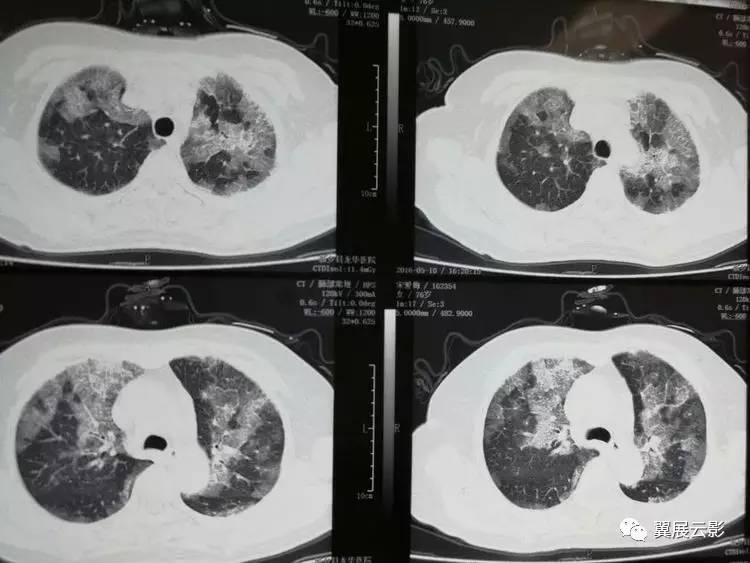

肺蛋白沉积症是一种罕见的疾病,它会导致异常蛋白质在肺部沉积,影响呼吸功能。作为一名医生,我亲眼目睹了许多患者因此疾病而受到困扰。在这篇文章中,我将探讨肺蛋白沉积症带来的挑战以及我们应对这些挑战的方法。

肺蛋白沉积症的早期症状往往不明显,容易被忽视。然而,及早发现并进行诊断和治疗是至关重要的。我们需要通过临床检查、影像学和组织活检等手段来确定诊断,并针对患者制定个体化的治疗方案。药物治疗、支持性护理和康复训练都是有效的治疗手段。